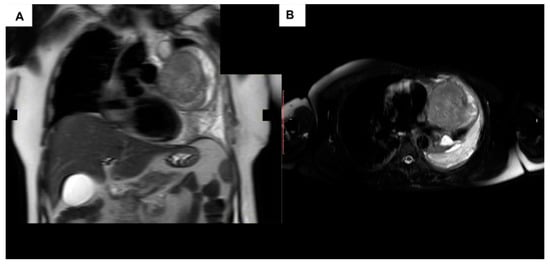

- Aroshidze, B.; Boyapati, L.; Pokhrel, A.; Gotlieb, V.; Khan, A.; Erdinc, B.; Cheema, M.A. Yolk Sac Tumor in the Anterior Mediastinum Presenting as Acute Pericarditis. Am. J. Case Rep. 2022, 23, e932616. [Google Scholar] [CrossRef]